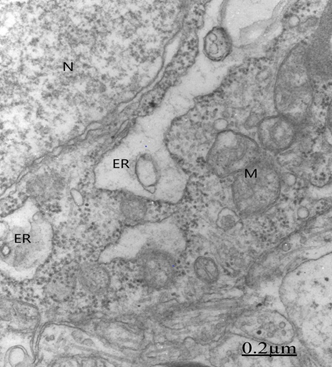

Electron microscopy images of astrocytes at low magnification show nerve cells charged of numerous lipofucsin granules (Figure 11). Besides, we report edematous and ischemic oligodendrocytes (Figure 12).25,26

Figure 12 Brain traumas, hematoma subdural. Severely edematous oligodendrocyte showing the nucleus (N) and lacunar enlargement of endoplasmic reticulum (ER), swollen mitochondria (M) and dense body (DB). The associated and degenerated myelinated axons show granular precipitation of axoplasm (Ax), and enlargement of periaxonal space (short arrow). The arrowhead indicates the axolemmal membrane.